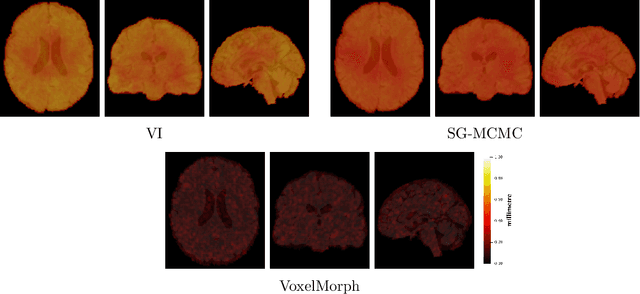

Abstract:We develop a new Bayesian model for non-rigid registration of three-dimensional medical images, with a focus on uncertainty quantification. Probabilistic registration of large images with calibrated uncertainty estimates is difficult for both computational and modelling reasons. To address the computational issues, we explore connections between the Markov chain Monte Carlo by backpropagation and the variational inference by backpropagation frameworks, in order to efficiently draw samples from the posterior distribution of transformation parameters. To address the modelling issues, we formulate a Bayesian model for image registration that overcomes the existing barriers when using a dense, high-dimensional, and diffeomorphic transformation parametrisation. This results in improved calibration of uncertainty estimates. We compare the model in terms of both image registration accuracy and uncertainty quantification to VoxelMorph, a state-of-the-art image registration model based on deep learning.